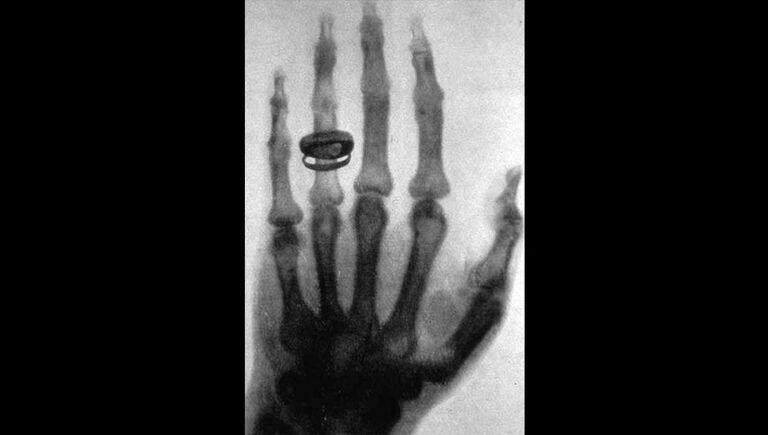

Вильгельм Конрад Рентген изучал электрические разряды и свойства катодных лучей в стеклянных вакуумных трубках, часто допоздна засиживаясь на работе. Так было и 8 ноября 1895 года, когда, выходя вечером из лаборатории, он заметил странное свечение. Это светился экран из синеродистого бария, за которым находилась катодная трубка: физик забыл ее обесточить по окончании опыта. Рентген выключил трубку — и свечение исчезло.

Это так заинтересовало ученого, что он начал экспериментировать. Ставил перед трубкой разные предметы и проверял, отражают они лучи или пропускают. В конце концов Рентген поместил перед трубкой свою руку и заметил, что она просвечивает на изображении, проецируемом на экране.

После этого исследователь заменил трубку фотографической пластиной и получил первую рентгенограмму. Это был снимок руки его жены, который впоследствии облетел весь мир. В 1901 году Рентген получил за свое открытие Нобелевскую премию по физике.

Снимок, сделанный Рентгеном 23 января 1896 года